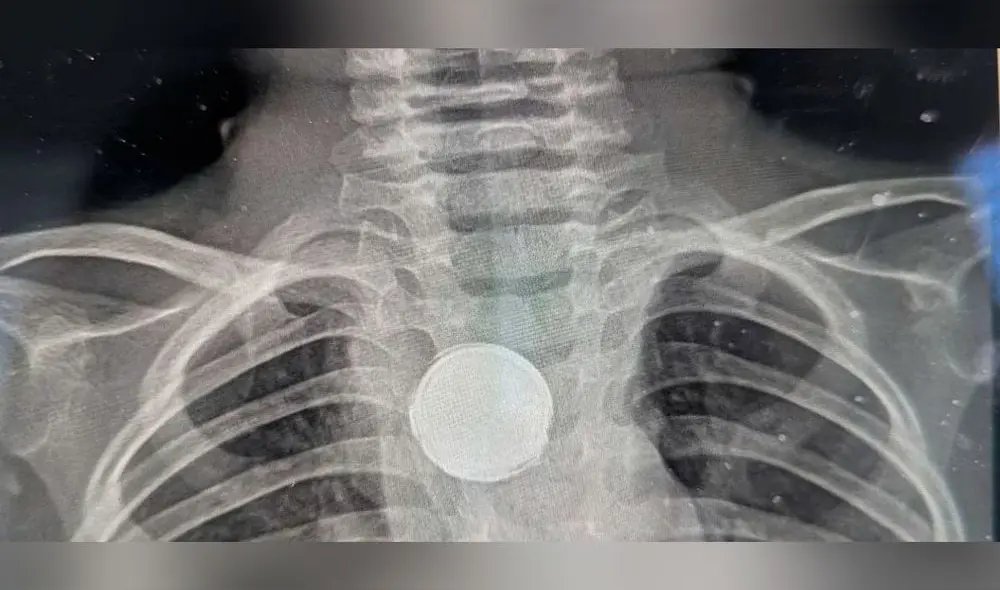

Radiografía de toraz y sorpresa

“Le vi poner una mirada extraña”, reveló Erica, a quien los médicos preguntaron si Luke se había tragado una moneda o si usaba un collar con un botón, a lo que ella respondió con una negativa.

En la radiografía del niño demostró que una pila permanecía atascada en su esófago. Foto: Clarín